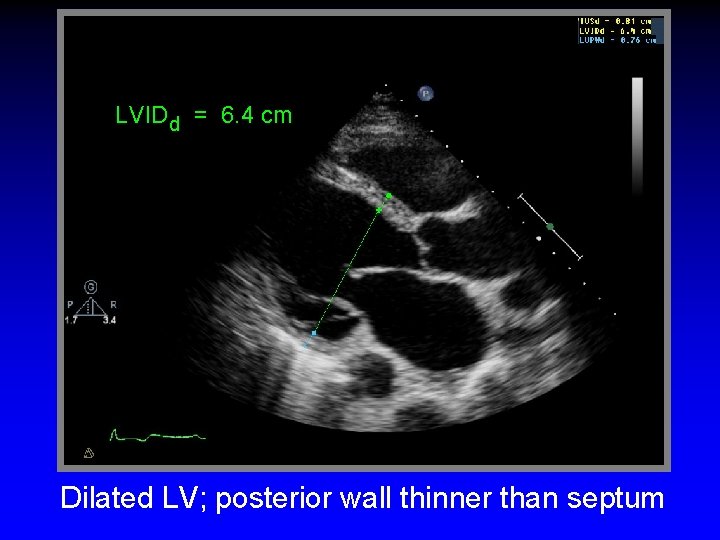

LVIDd = 6. 4 cm Dilated LV; posterior wall thinner than septum